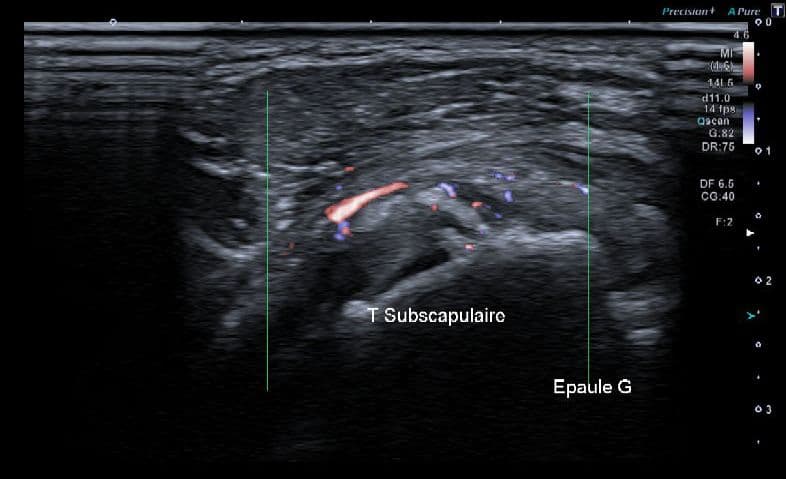

Résorption calcique aigue du tendon sous-scapulaire

Échographie

Calcification non atténuante fragmentée de 15 mm, franchement active en Doppler, et sensible à la pression sous la sonde.